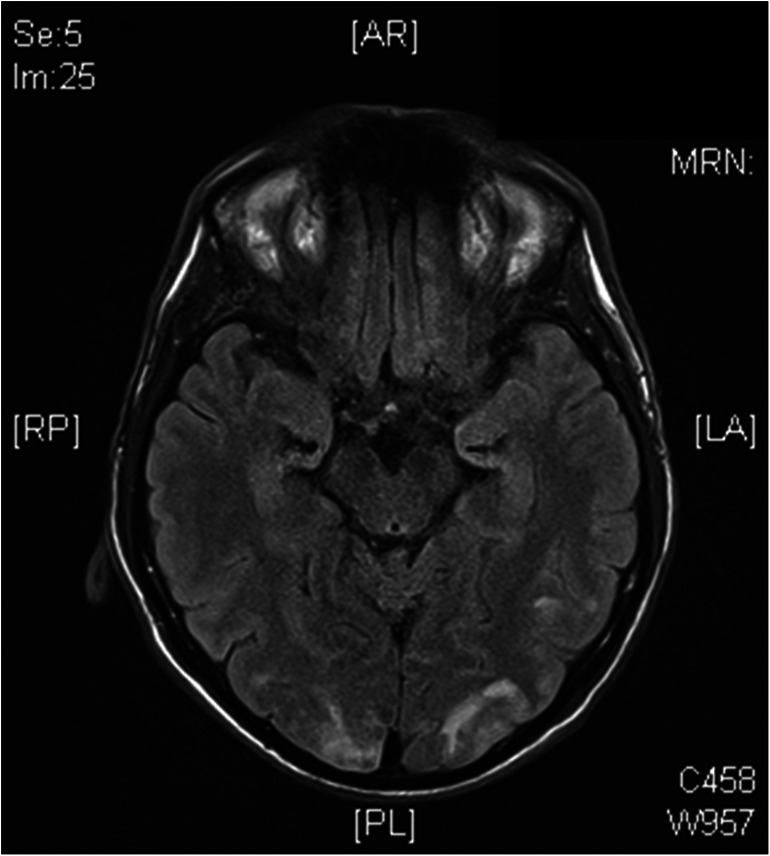

Further complications post-BMT resembled typical sickle cell complications: seizures and visual impairments compatible with posterior reversible encephalopathy syndrome (PRES) by NMR imaging (Fig. 1), diabetes insipidus centralis due to the PRES or CSA, and diabetes insipidus renalis due to foscarnet turned out to be manageable. Following recovery, further follow-up was uneventful through 2.5 years, without immunosuppression and according to hemoglobin analysis complete correction of the hemoglobinopathy.

Fig. 1.

NRM brain image of the patient 40 days post-BMT with occipital edema compatible with posterior reversible encephalopathy syndrome (PRES)